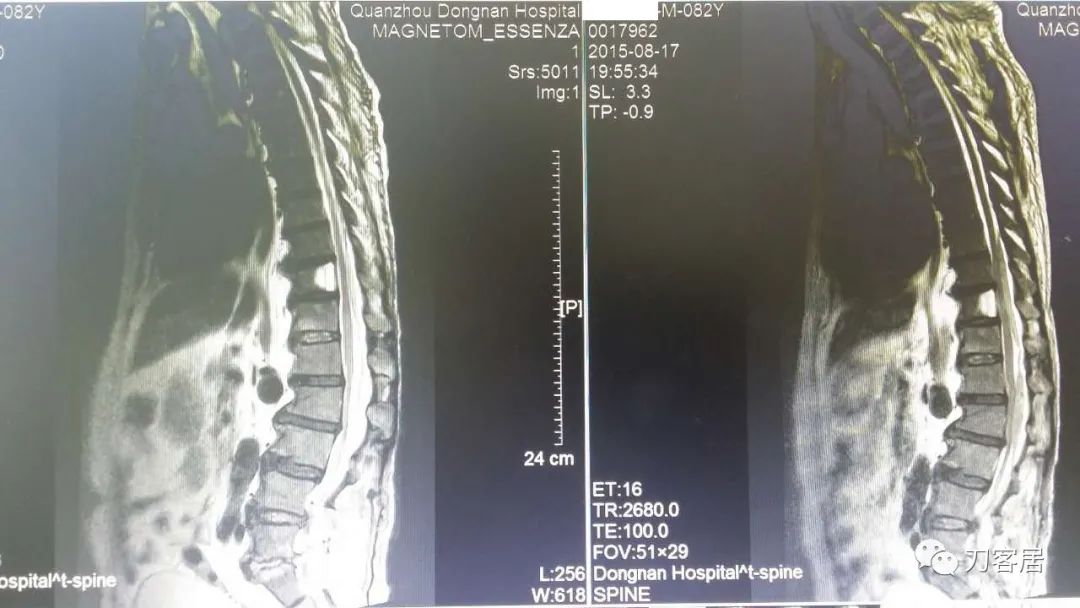

加注图10: 腰1-2椎管内后方可见梭形占位信号改变。

加注图11. 腰1-2椎管内后方可见梭形占位信号改变。

加注图14. 胸9-10椎管内后方高信号占位病变,考虑血肿形成。

加注图15. 胸9-10椎管内后方高信号占位病变,考虑血肿形成。

加注图16. 胸9-10椎管内后方高信号占位病变,考虑血肿形成。

加注图17. 胸9-10椎管内后方高信号占位病变,考虑血肿形成。